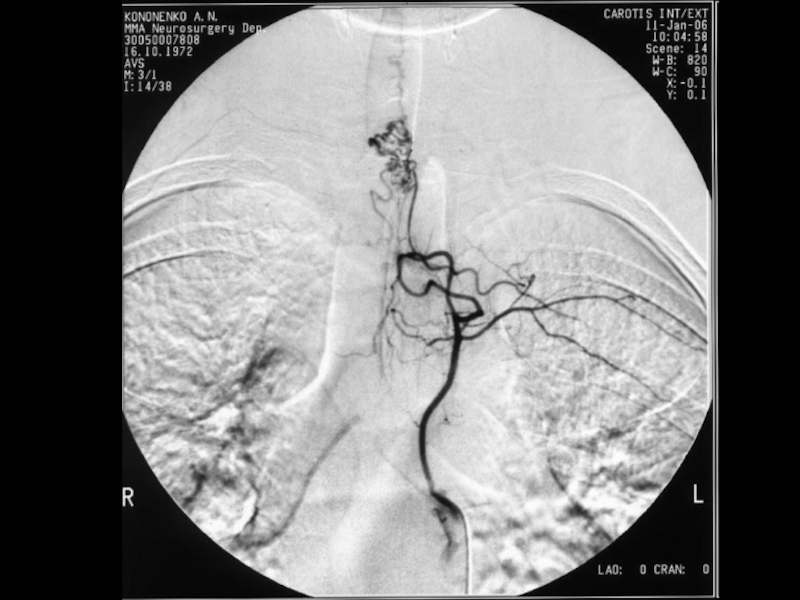

Слайд 38Метастатическое поражение

позвоночника. Сцинтиграфия скелета

с остеотропным РФП

99mТс-пирфотехом

Метастатическое поражение позвоночника. Сцинтиграфия скелета с остеотропным РФП 99mТс-пирфотехом